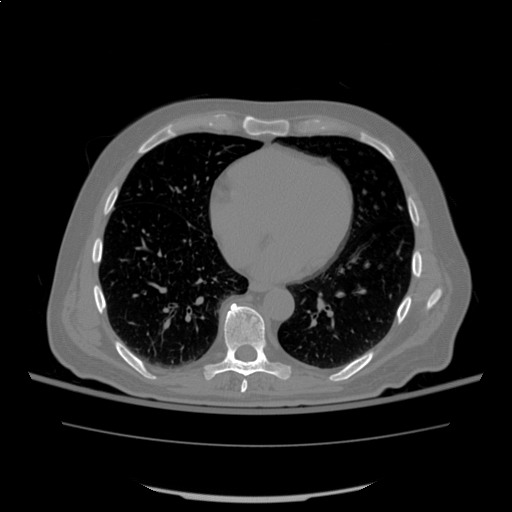

Attached are the image, they all look good to me.

Attached Thumbnails

Click image for larger version

Name:	image.png

Views:	3344

Size:	44.4 KB

ID:	562

Sample of the actual images attached.

The errors spits out for every single one of the images when I try to load them.

Name:	1.png

Views:	3216

Size:	32.3 KB

ID:	568   Click image for larger version

Name:	2.png

Views:	3191

Size:	36.6 KB

ID:	569   Click image for larger version

Name:	3.png

Views:	3154

Size:	58.1 KB

ID:	570   Click image for larger version

Name:	4.png

Views:	3176

Size:	68.5 KB

ID:	571   Click image for larger version

Name:	5.png

Views:	3210

Size:	59.1 KB

ID:	572